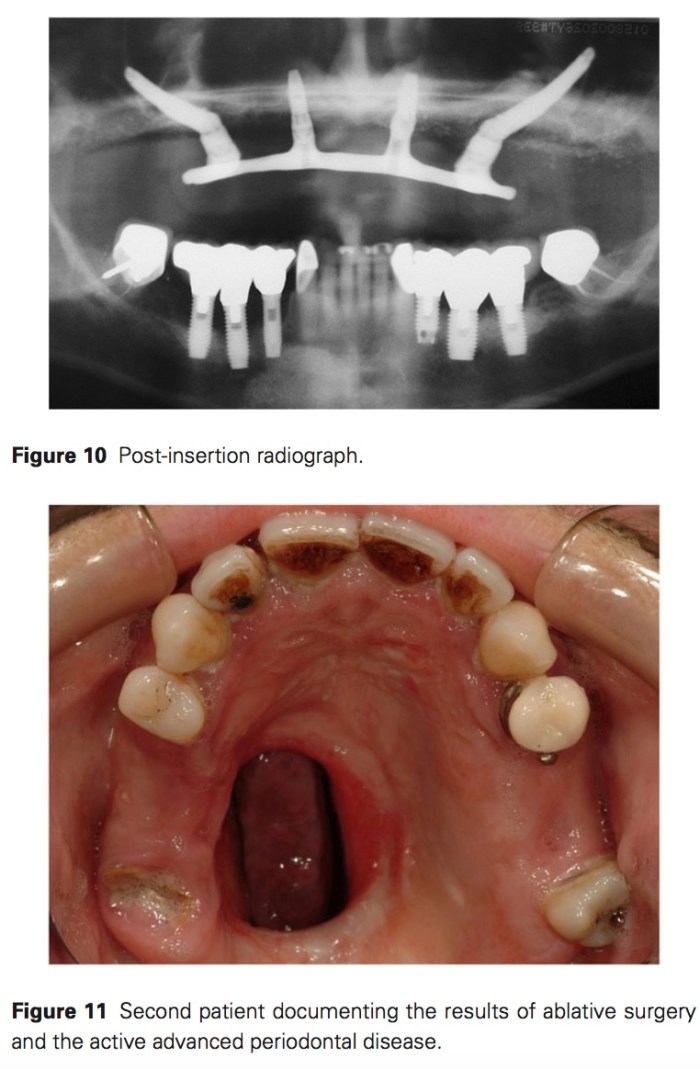

我們比較少看到zygomatic implant的案例文章,主要是因為不好做,另外就是做起來很難做得好看。但是在一些平常少見的情形之下,像是之前植牙失敗導致骨缺損,或是上顎的先天或是後天手術造成的缺損,需要使用zygomatic implant。在不侵犯到鼻竇腔的狀況下,其實術後的不適並不會比同時植很多顆植體有差異。